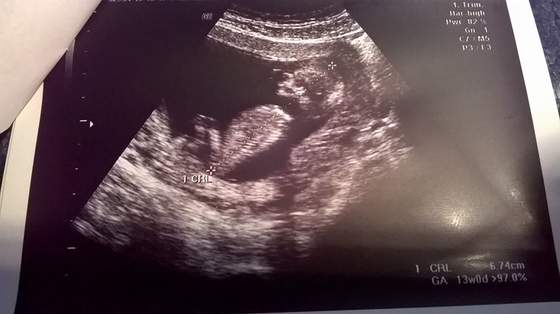

No to czas się pochwalić moim maleństwem zdjęcie z poniedziałkowej wizyty 5

Zobacz załącznik 715982

w dniu badania według ostatniej miesiączki to był 12 tydzień i 2 dni a według usg 13 tydzień więc dzidziol jest trochę większy